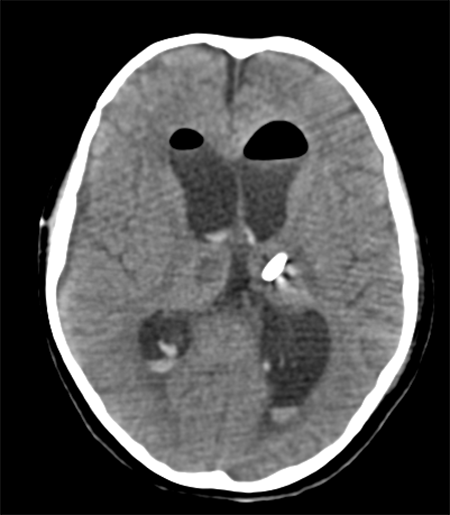

Caso ilustrativo n°5: Houkin tipo 5(Figura 5)

Paciente de 9 años de edad, amaurótica bilateral, con diagnóstico de tumor supraselar hipotálamo-quiasmático, se realizó cirugía de exploración y exéresis de tumor vía transcallosa. Presentó a las 12 hs deterioro del sensorio y crisis convulsiva, con diagnóstico de hidrocefalia aguda se realizó cirugía de colocación de drenaje ventricular al exterior. Paciente no presentó mejoría en post quirúrgico por lo que se realizó imagen control evidenciando catéter fuera de cavidad. Requirió re-operación para re-colocación de catéter.

Figura 5: Imagen por Tomografía Cerebral computada que muestra catéter proximal fuera de cavidad ventricular.

Se considera Houkin tipo 5, ya que fue tratamiento insuficiente de la hidrocefalia debido a un error médico.